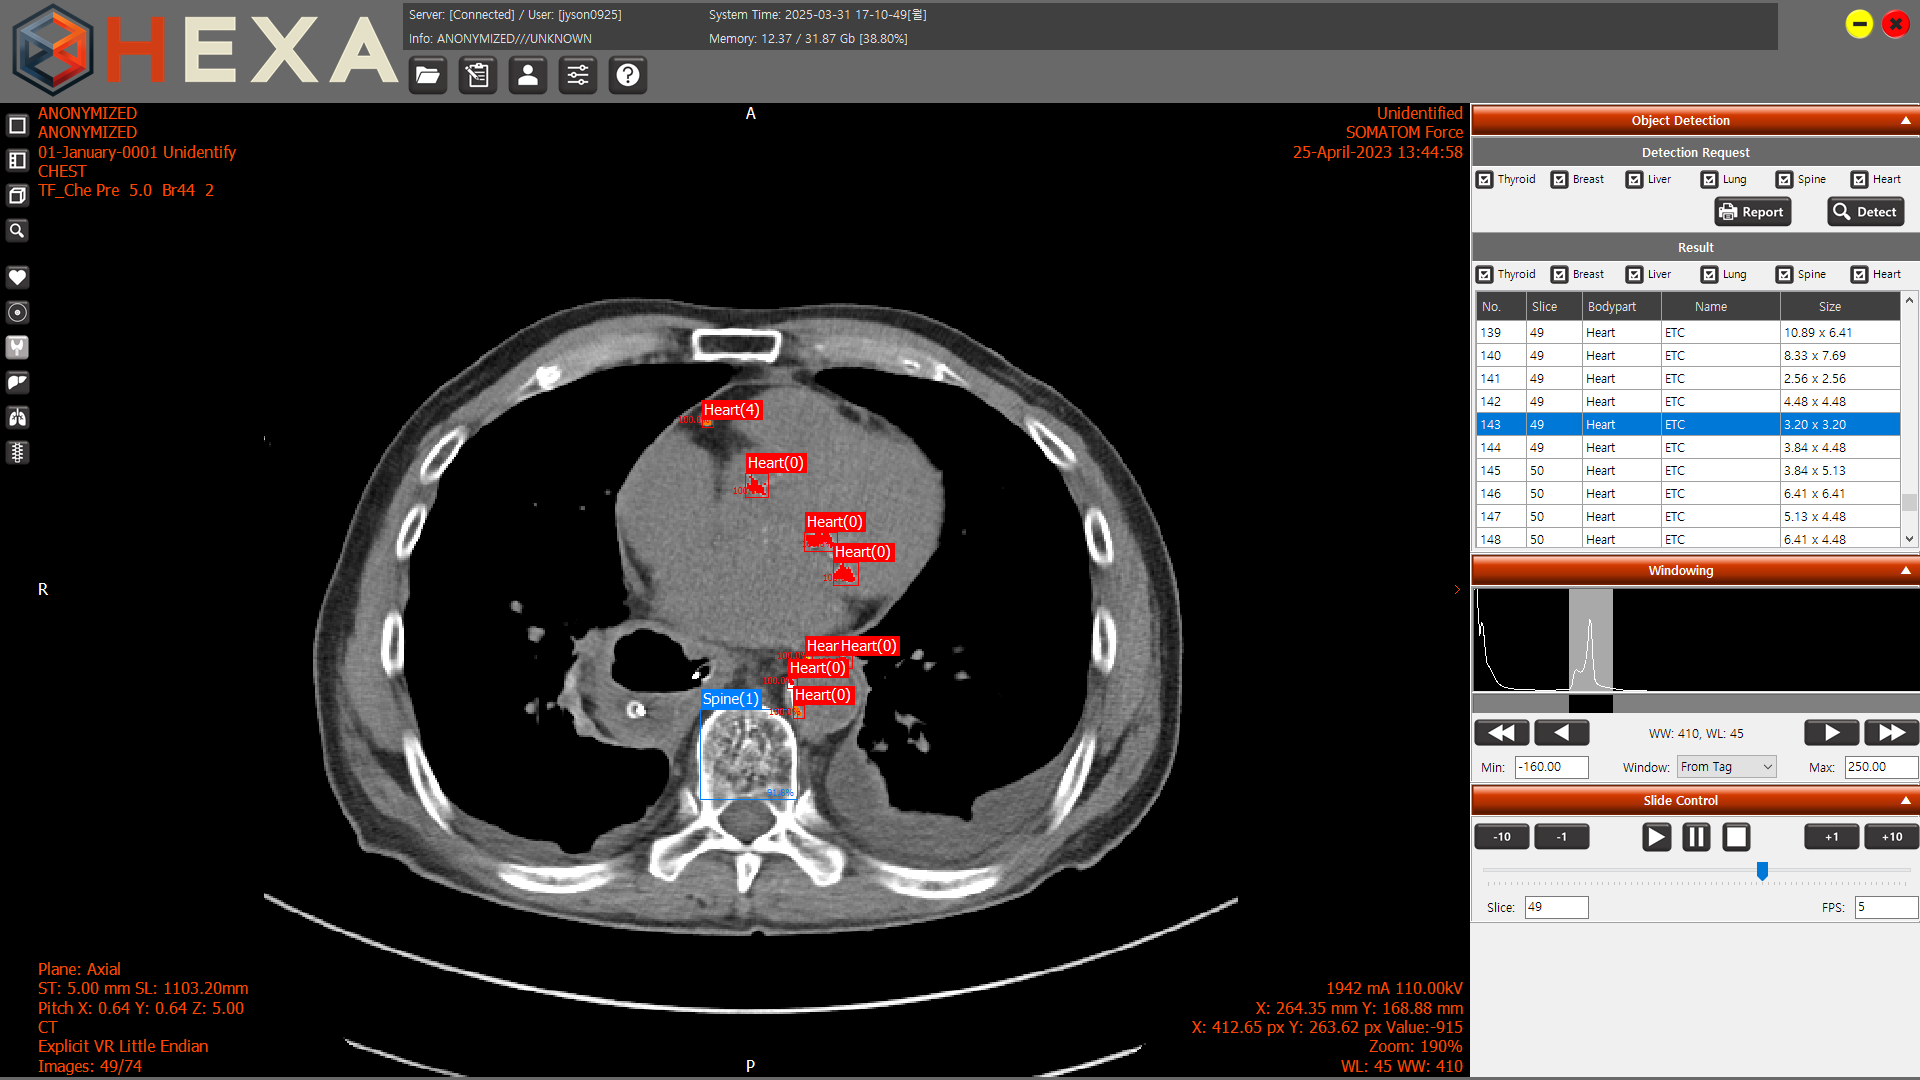

[메디칼타임즈=이인복 기자] 엑스큐브(XCube)가 17일부터 19일까지 서울 코엑스에서 열리는 국제 병원 및 헬스테크 박람회(K-HOSPITAL+HEALTHTECH FAIR, KHF 2025)에서 의료영상 솔루션 HEXA를 전시한다.

HEXA는 흉부 CT 데이터를 기반으로 갑상선, 심장, 폐, 간, 유방, 척추 등 6개 주요 장기의 이상 소견을 AI가 자동으로 검출하고 시각화하는 디지털 헬스케어 소프트웨어다.